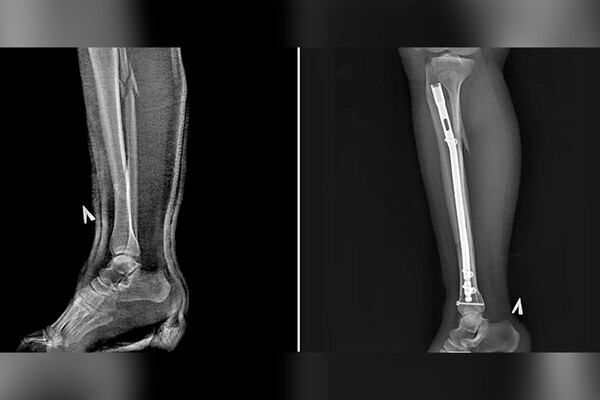

Пациентке диагностировали оскольчатый перелом костей голени, большой берцовой и малой берцовой костей. Травматологи под анестезией осуществили сращивание костей, закрепив их штифтом и винтами.

«Такой способ позволяет уйти от привычного гипса и исключить риск вторичного смещения, а также последствий в виде тромбоза, остеопороза, артроза», — пояснили медики.

Женщина смогла наступать на поврежденную ногу уже в первый день после операции. Через год пациентке предстоит еще одно вмешательство, на котором врачи удалят все металлические конструкции из ее ноги.